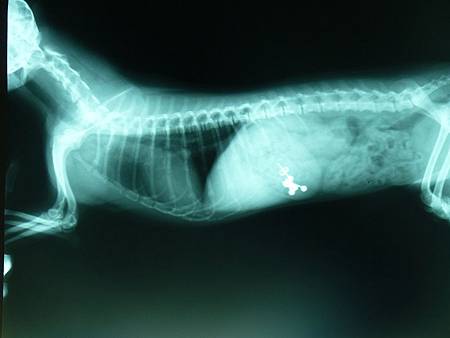

診斷異物的方法,消化道x光檢查是必須的,

x光檢查分為一般攝影與照影劑攝影,石頭、鐵釘、

針,等...這些密度較高的物品,在一般x光攝影就

可以診斷出來,但是如果是線、水果籽如:龍眼、

桃子、酸梅等...、塑膠密度較小的物品,就無法在

一般x光攝影下被檢查出。

動物吞食了鐵釘與耳環的x光片(嘉興動物醫院)